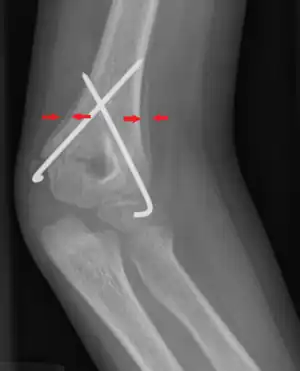

| Periosteal reaction on a healing supracondylar fracture | |